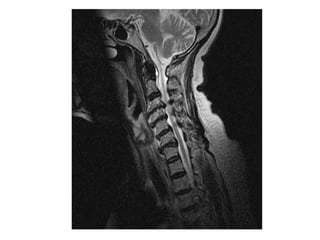

P. E.  65 years old He presented with a long history of immobility and progressive deterioration in his level of function.  Unable to feed himself, turn in bed or do any activities of daily living.  He had been bed bound for about a month. He had clear signs of cervical myelopathy

Conclusion The managementof moderate & severe CSM is surgical. There is no role for conservative management unless the patient is medically unfit for surgical intervention or there are no surgical lesions. NO ROLE FOR STEROIDS Operation can be performed safely from either an anterior or posterior approach. Early sustained recovery has been encouraging in our small series.

Results   Three patients underwent anterior cervical discectomy and fusion and 3 had cervical laminectomy performed.  Five patients improved significantly post operatively with sustained neurological improvement over 6 months of the operation.  There was one death due to pulmonary embolism 3 weeks after surgery.